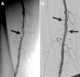

Angioplasty, also known as balloon angioplasty and percutaneous transluminal angioplasty (PTA), is a minimally invasive endovascular procedure used to widen narrowed or obstructed arteries or veins, typically to treat arterial atherosclerosis. A deflated balloon attached to a catheter (a balloon catheter) is passed over a guide-wire into the narrowed vessel and then inflated to a fixed size. [Source: Wikipedia ]